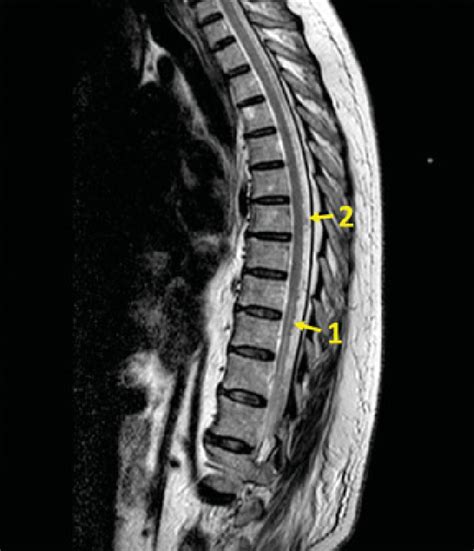

So, if you suspect there’s an issue with the medullary cone region , how do doctors figure it out, and what can be done? Diagnosis typically starts with a thorough medical history and a detailed neurological examination. Your doctor will be looking for specific patterns of weakness, sensory loss, and reflex changes in your legs and trunk, as well as assessing bowel and bladder function. To get a clear picture of what’s going on inside, imaging studies are crucial. Magnetic Resonance Imaging (MRI) is usually the gold standard. It provides detailed images of the spinal cord, nerve roots, and surrounding structures, allowing doctors to identify things like tethered cords, disc herniations, tumors, or other abnormalities affecting the conus medullaris. Sometimes, a CT scan might be used, especially if MRI is contraindicated or to get a different perspective on bony structures. In some cases, electromyography (EMG) and nerve conduction studies might be performed to assess the electrical activity of the nerves and muscles, helping to pinpoint the extent of nerve damage.